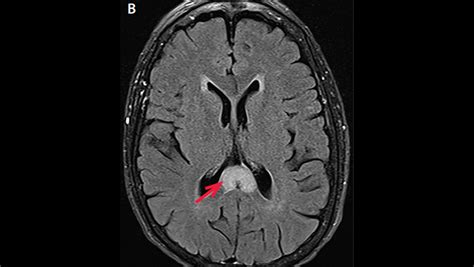

Due to its high concentration of neural pathways, the splenium of corpus callosum is a frequent area of interest in neuroradiology. Magnetic Resonance Imaging (MRI) is the gold standard for evaluating this region. Changes in the integrity of the splenium can be a marker for a variety of neurological conditions, ranging from developmental disorders to acute inflammatory processes.

When clinicians observe signal abnormalities in the splenium, they often look for what is termed "reversible splenial lesion syndrome" (RESLES). This condition often presents with acute onset of symptoms such as confusion, seizures, or vision changes, but interestingly, the lesions often resolve over time without permanent damage. This highlights the unique vulnerability and resiliency of the splenium to metabolic and inflammatory stressors.

• Multiple Sclerosis (MS): Often manifests as "Dawson’s fingers," where plaques extend into the corpus callosum.

• Marchiafava-Bignami Disease: A rare condition, typically associated with chronic alcohol consumption, that leads to necrosis of the callosum.

• Traumatic Brain Injury (TBI): Due to the shear forces exerted during head impact, the splenium is a common site for diffuse axonal injury.

• Infectious Processes: Viral encephalitis or other systemic infections can occasionally cause temporary lesions in the splenial region.